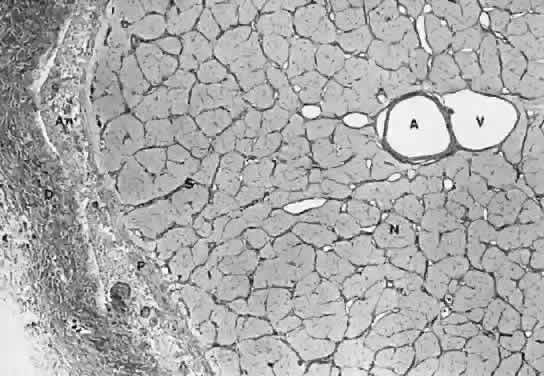

Fig. 6. Cross-section of the optic nerve. (A) central retinal artery; (V) central retinal vein; (S) connective septa from the pia mater; (P) pia mater; (An) arachnoid cell nests; (D) dura mater; (N) axon bundles intermingled with glia cell nuclei.

The intraorbital portion of the optic nerve is enclosed by three sheaths that are continuous with the meninges of the CNS: the dura mater, arachnoid, and pia mater (Fig. 6). The outermost of these is the dura mater, a dense collagenous and elastic tissue. Anteriorly, the dura mater frays and inserts into the sclera and rectus muscle sheaths along with the ciliary arteries and nerves. Posteriorly, the dura mater divides into two layers. One of these layers fuses with the periosteum of the bony canal and with Zinn's annulus at the apex of the orbit; the remaining layer is tightly adherent to the bone of the canal and the optic nerve. When the optic nerve passes the cranial foramen of the canal, the dura mater becomes the periosteum of the sphenoid bone. Therefore, even small lesions that occur within the canal or at its openings will compress and damage the optic nerve.

The pia mater lies tightly on the surface of the nerve and consists of collagenous fibers, elastic fibers, and a fused glial layer. The pia mater invests the nerve and sends fibers into it to form the characteristic septa. The septa are separated from the surrounding nervous tissue by the foot processes of the astrocytes, but they are continuous with the collagenous adventitial sheaths of the central retinal artery and vein within the optic nerve. The pia mater joins the sclera and choroid anteriorly; posteriorly, it continues through the optic foramen to form the single sheath around the intracranial portion of the optic nerve.

The arachnoid is composed of trabeculae of collagenous and elastic fibers lined by meningothelia. It contains numerous vessels, along with some fibroblasts and histiocytes. The meningothelia often proliferate in a concentric pattern and form onion-like structures, with or without calcification, known as the psammoma bodies or corpora arenacea, respectively.